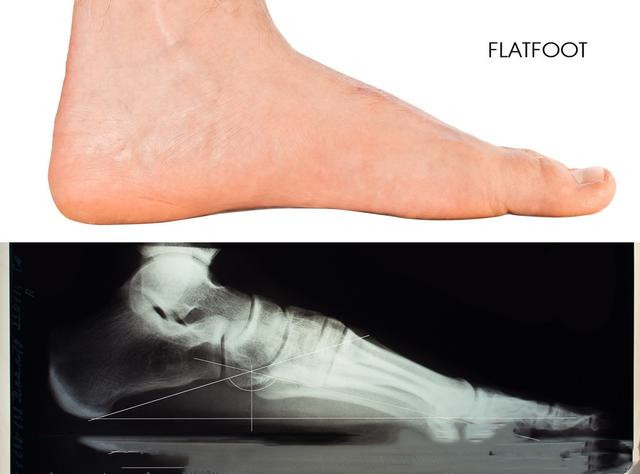

一、 先来了解下什么是“扁平足”

如何判断自己是不是扁平足呢?其实很简单,把鞋子脱了以后光脚站在地上,如果整个脚底都贴在地面上,那你就是典型的扁平足了。再一个就是从侧面观察自己的脚底,正常人的脚是有明显的弯曲的足弓的,而扁平足则是一条直线。

功能性扁平足也叫柔性扁平足,是扁平足中最为常见的一种。它发生于儿童时期,并且持续到成年后。在坐着的状态下,功能性扁平足和正常脚型相差不大,也有弯曲的足弓,但是一旦站立,脚开始称重以后就会表现成扁平。

结构性扁平足又称为刚性扁平足,所谓刚性就是说无论是站着还是坐下都没有足弓。这种扁平足是真的平,多发生在胫骨后肌肌腱功能障碍患者的身上,不一定是两只脚同时患有,也可能只存在于一只上。这种扁平足是由骨骼发育畸形造成的,常伴随有疼痛感,极难修复。